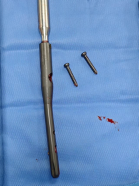

先小心翼翼取出嵌在盆腔的钢钉,避免损伤血管;

将患者自身修剪后的股骨头骨质填补到髋臼破损处,重建"地基";

植入特制加长股骨柄假体,像"钢筋"一样牢牢固定新关节。